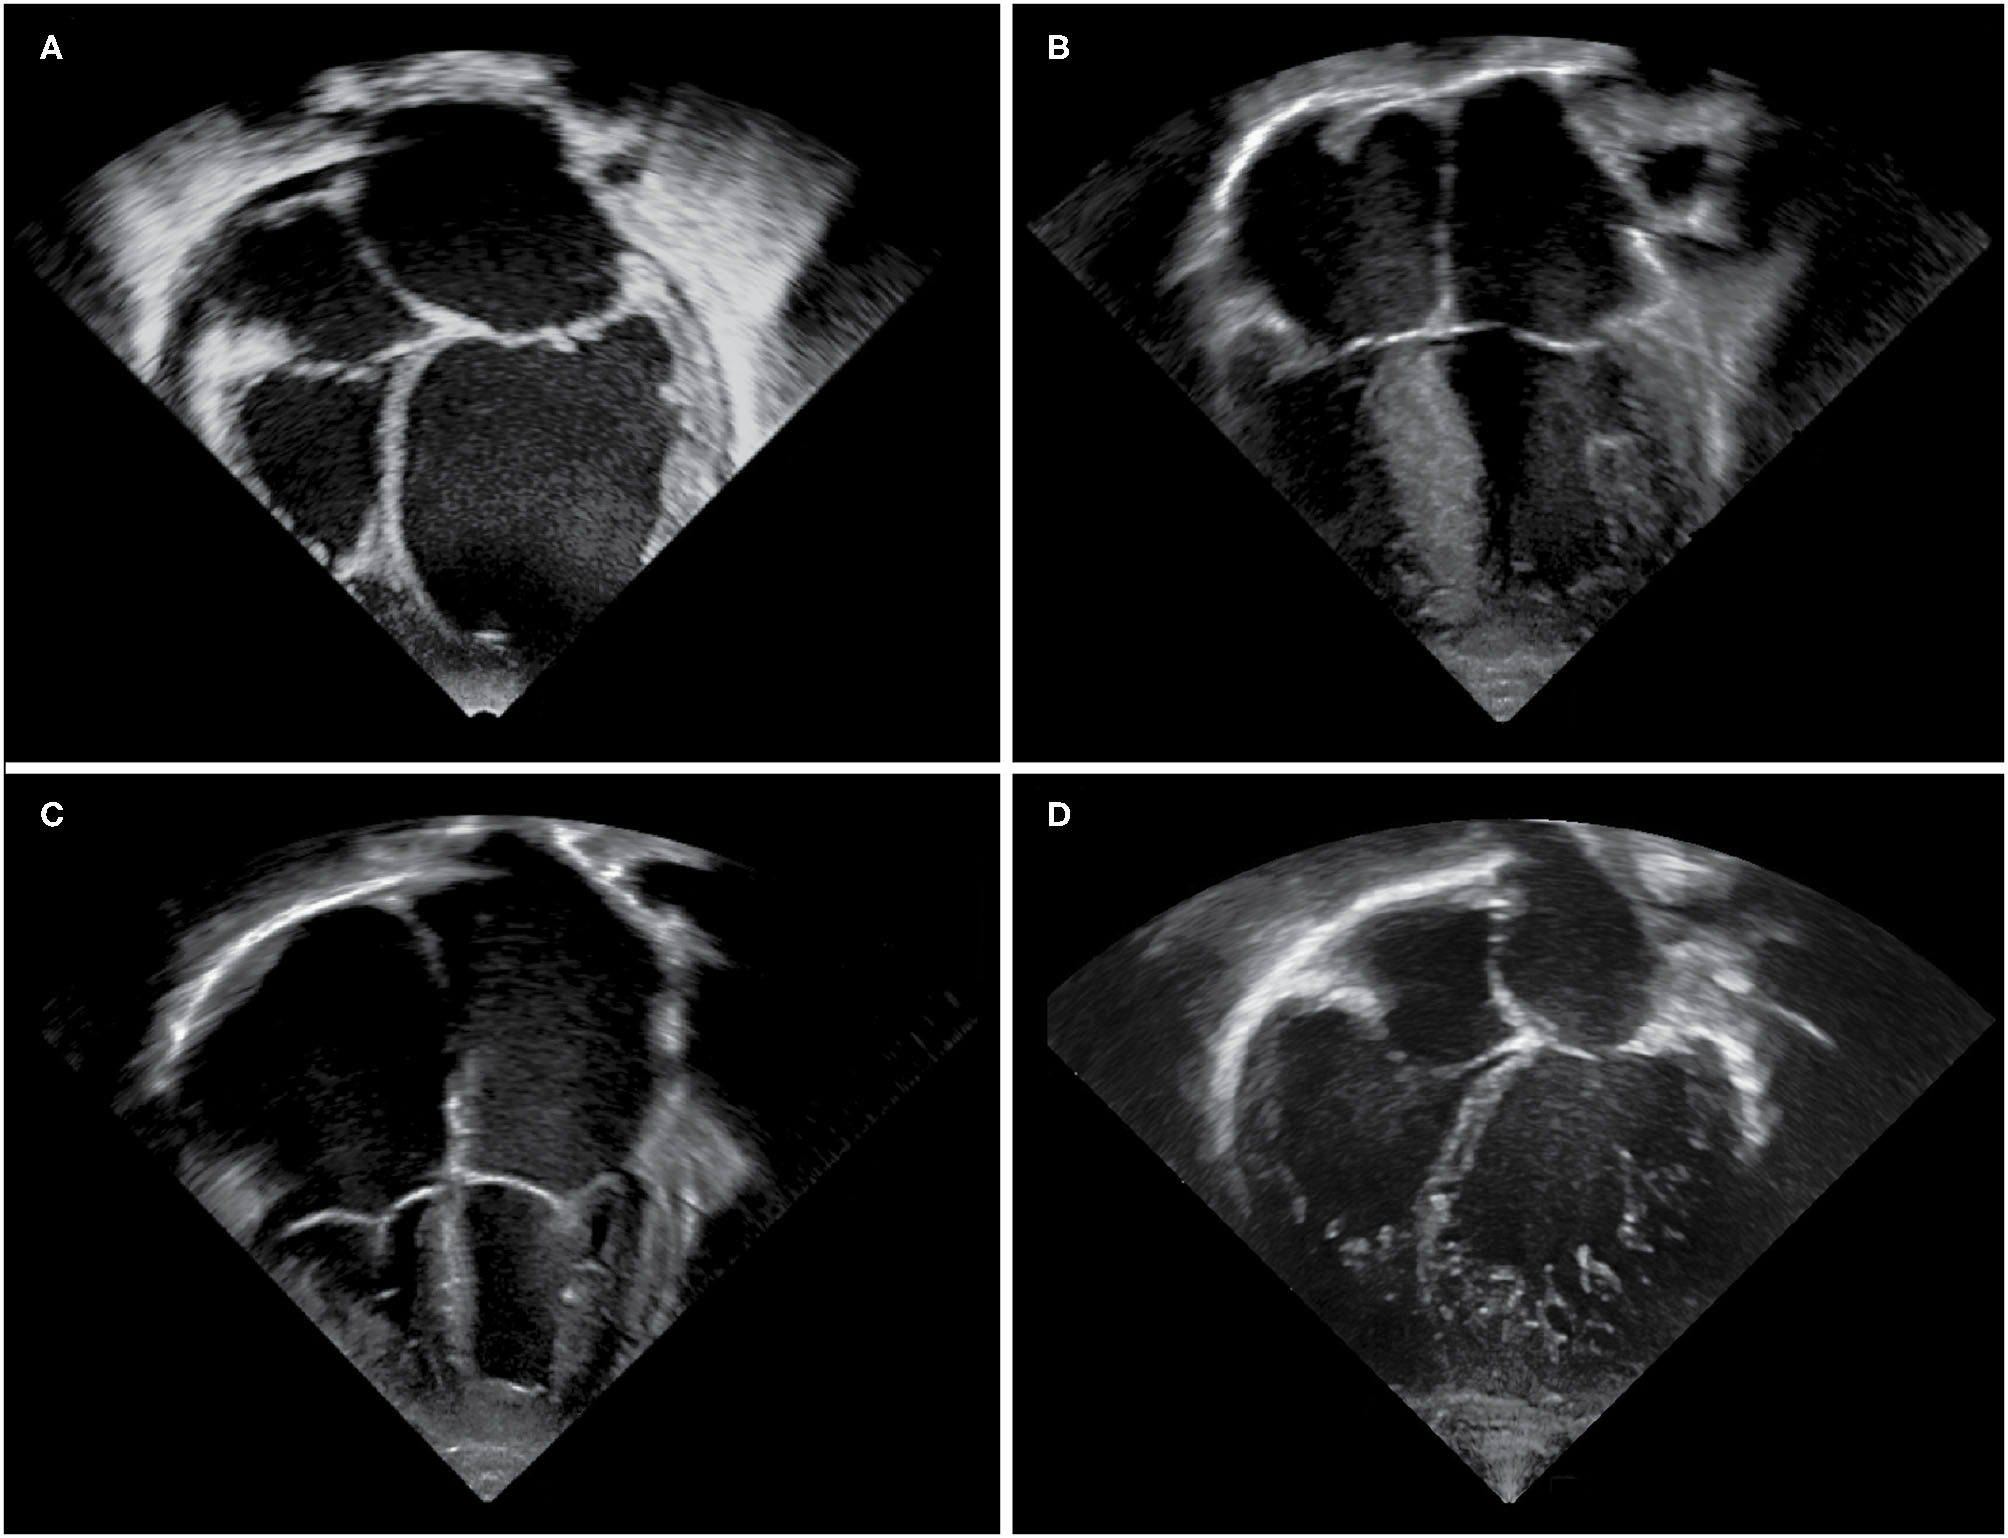

Paediatric cardiomyopathies form an uncommon and heterogenous group of disorders, which are characterised by structural, mechanical, and electrical abnormalities of the heart muscle (1, 2). Aetiologies are diverse, and include infections, toxin exposure, tachyarrhythmias, genetic mutations, and underlying metabolic or neuromuscular disorders (16). Large population registries together with national and multicentre studies have contributed considerably to the increasing knowledge on epidemiology and outcomes of childhood cardiomyopathies (5, 724). The overall annual incidence is estimated at about 1 per 100,000 children, with a significantly higher incidence during the first 2 years of life (7, 17, 18). Dilated and hypertrophic cardiomyopathies are the most common types, whereas left ventricular non-compaction and restrictive cardiomyopathy occur less frequently (7, 17). Arrhythmogenic ventricular cardiomyopathy is rarely diagnosed during childhood and will not be discussed in this article. The terms dilated, hypertrophic, restrictive, and non-compaction depict different phenotypes (see Figure 1) and thereby assist in grouping cardiomyopathies, however they do not describe specific disease entities. The European Society of Cardiology classifies cardiomyopathies according to their predominant phenotype, but does not recognise left ventricular non-compaction as a separate entity, whereas the American Heart Association classifies cardiomyopathies according to their aetiology, with left ventricular non-compaction considered to be a separate entity (25, 26). Some children may present with a mixed phenotype, and cardiomyopathy phenotypes may undulate or transition during the course of disease (1, 12, 13, 27). This review summarises the most common forms of paediatric cardiomyopathies, with a focus on epidemiology and natural history.

Figure 1. Echocardiographic images of cardiomyopathy phenotypes. Apical four chamber views demonstrating (A) a dilated left ventricle and left atrium in a DCM patient, (B) hypertrophy of the interventricular septum and left ventricular free wall in a HCM patient, (C) massively dilated atria and small right and left ventricular cavities in an RCM patient, (D) an extensively trabeculated myocardium with a compacted and non-compacted layer and deep intertrabecular recesses most prominent at the left ventricular apex and free wall in an LVNC patient.